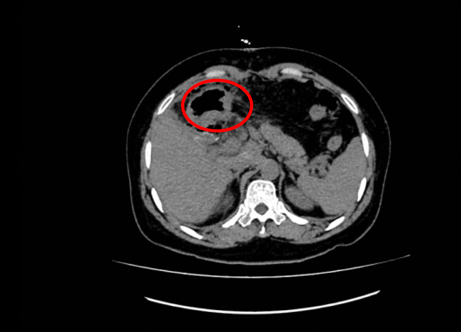

近日,由潘耀振教授主刀,带领王兴副主任及团队实施了手术。腹腔探查见患者肿瘤位于左肝,呈突出性生长,巨大的包块令人触目惊心,与周围组织重度粘连,肿瘤压迫了胃、胰腺、结肠等重要脏器,但肿瘤医院的外科专家们凭借精湛的技术,术中精细操作、默契配合,成功完成了扩大左半肝及肿瘤的切除,取出的肿瘤尺寸达18x14cm,术中出血量极少,手术非常成功。

患者术后影像

术后,在肝胆外科护理团队运用快速康复管理及精心护理下,王女士的身体各项指标加快恢复,没有任何并发症发生,术后第二天就可以下床活动了。王女士及家属心怀感激,在潘耀振教授带领医护人员查房时,对治疗团队高超的医术、术前精心筹备和术中的专业操作竖起了大拇指,还感谢护理团队在术后护理中的细心周到与无微不至。